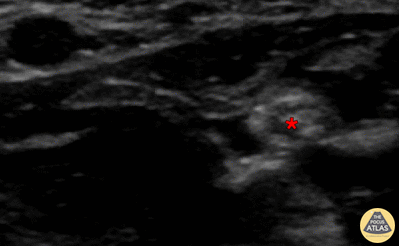

In-plane median nerve block, with needle seen entering from screen right (ulnar aspect), with anesthetic deposited deep to median nerve (*). the radial artery can be seen pulsating superficial to and screen left of (radial to) the nerve. Denver Health Ultrasound Fellowship